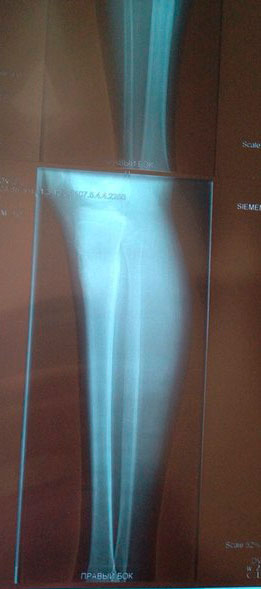

Рентген контроль в 81 день с момента снятия аппаратов.

Сращение железное, никаких ограничений! На физ-ру ходить можно! И ждём фото ножек девочки!